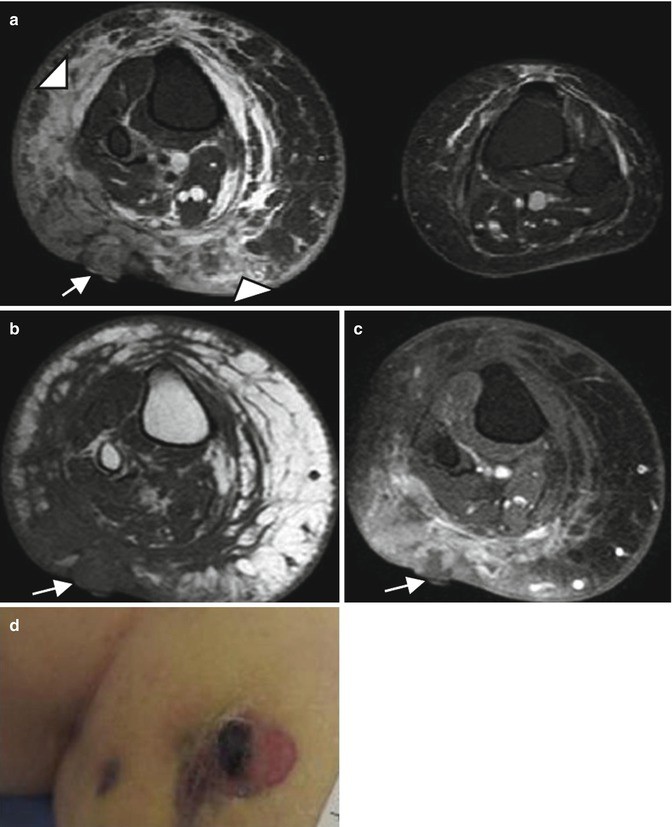

Stewart-Treves syndrome in a 66-year-old woman who was treated 20 years ago for uterus cervical cancer. (a) Axial T2-weighted MR image, with fat suppression. (b) Axial T1-weighted MR image. (c) Axial T1-weighted MR image after Gadolinium contrast administration, with fat suppression. (d) Clinical photograph. (a) Axial T2-W fat-suppressed MR images reveals an enlarged right extremity with subcutaneous edema (arrowheads) (a–c) Nodular mass of low signal intensity on T1, with low to intermediate and heterogeneous signal intensity on T2 and a heterogeneous enhancement (arrows) representing the angiosarcoma. (d) Clinical photograph shows the purplish skin lesion